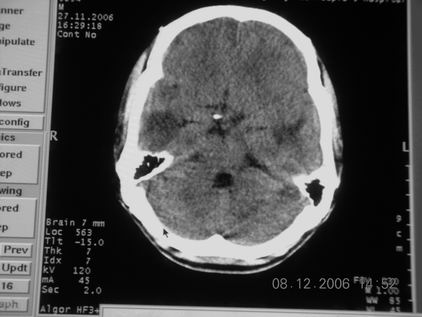

标题: CT11164:男,46岁,白血病患者,,大家看看. [打印本页]

标题: CT11164:男,46岁,白血病患者,,大家看看.

以前的片子,病史忘了,男,46岁,白血病患者,后来到中山二院诊断为

谁见过白血病中枢系统改变是怎么样的吗?

多发性脑脓肿?

白血病脑浸润。

支持白血病脑浸润.

1 多发脑脓肿可能性大.>2 白血病浸润.

白血病脑浸润。没见过!但结合病史应首先考虑此病。

支持白血病脑浸润

结合病史考虑白血病脑浸润。

结合白血病病史,支持考虑白血病脑浸润。

结合病史考虑白血病脑浸润